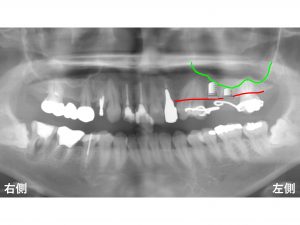

現在の骨の位置が以下の赤線 です。

次に上顎洞 は以下です。

現在の骨の高さは、以下です。

上顎の2歯欠損のうち

手前側は、ある程度の高さのインプラントを埋入することは可能ですが、

その奥の骨の高さは非常に少ないことが分かります。